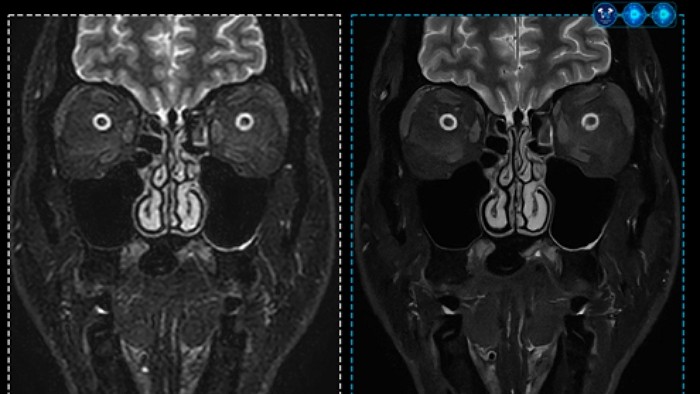

Meanwhile, Philips is supporting the entire healthcare delivery system—including diagnosis, treatment, and clinical decision-making—through a variety of AI-powered healthcare solutions. By providing predictive analytics based on AI in key areas such as radiology, patient monitoring, and data management, Philips helps healthcare professionals make quicker and more accurate decisions. These solutions also contribute to optimizing hospital workflows, developing personalized treatment plans, and improving equipment operation efficiency, thereby accelerating digital transformation in the healthcare field.